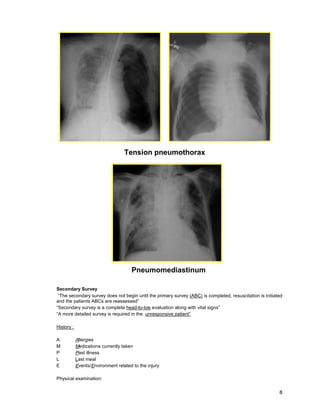

Secondary Survey

“The secondary survey does not begin until the primary survey (ABC) is completed, resuscitation is initiated

and the patients ABCs are reassessed”

“Secondary survey is a complete head-to-toe evaluation along with vital signs”

“A more detailed survey is required in the unresponsive patient”

Tension pneumothorax

Pneumomediastinum